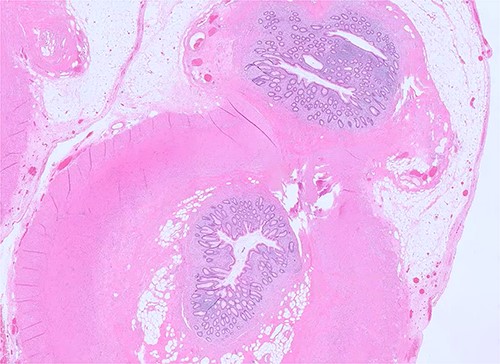

A 27-year-old male complaining of abdominal pain was admitted to the emergency room. He had experienced pain in the right iliac fossa the day before, but had not reported any other digestive or extra-digestive signs at home. Clinical examination revealed a positive McBurney sign, and blood tests showed neutrophil-predominant hyperleukocytosis and increased C-reactive protein. An abdominal CT scan revealed a swollen latero-caecal appendix, containing two stercoliths at its base and a small fluid collection at its tip (Fig. 1). Appendectomy was performed, confirming the presence of two latero-caecal appendicular bases and two stercoliths. Both appendices were ligated individually (Fig. 2). A search for Meckel's diverticulum was negative. Histopathological examination confirmed the diagnosis (Fig. 3). The patient recovered without any complications.

Microscopic examination of the specimen reveals two appendices with two separate lumens, partially sharing the muscularis layer, the sub-serosa, and the serosa (H&E, ×100).